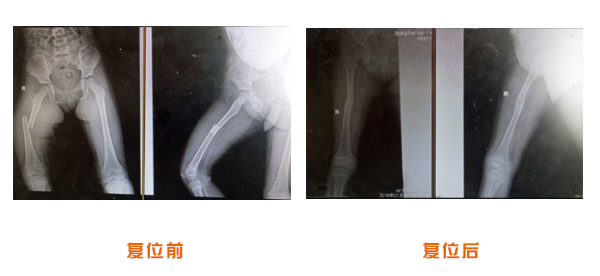

肘關節脫位骨折治療前后對比